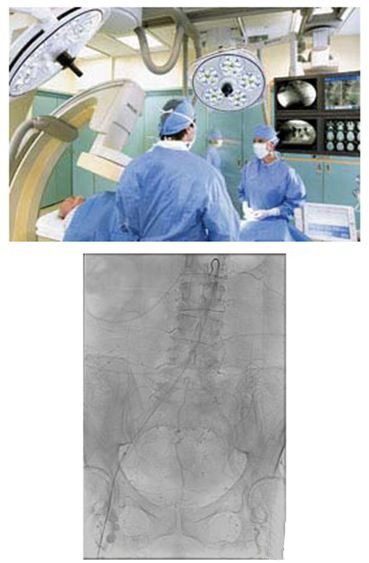

當(dāng)患者在躺手術(shù)臺(tái)上,介入放射學(xué)醫(yī)師會(huì)引導(dǎo)導(dǎo)管運(yùn)動(dòng),通過(guò)一系列錯(cuò)綜復(fù)雜的動(dòng)脈血管。當(dāng)醫(yī)師引導(dǎo)導(dǎo)管通過(guò)動(dòng)脈網(wǎng)到達(dá)冠狀動(dòng)脈和所關(guān)注的區(qū)域時(shí),醫(yī)師可從顯示器上得到實(shí)時(shí)反饋,從而小心地移動(dòng)導(dǎo)管進(jìn)行介入治療。

大量手術(shù)都屬于介入類(lèi)別,包括在動(dòng)脈、靜脈、淋巴或膽管系統(tǒng)利用血管成形術(shù)放置導(dǎo)管、放置血管支架、進(jìn)行導(dǎo)管栓塞、血栓溶解和化療或?qū)Ыz栓塞。臨床醫(yī)生在診斷和治療心血管疾病和腫瘤方面發(fā)現(xiàn)了利用介入放射學(xué)的重大機(jī)遇。無(wú)論他們利用血管成形術(shù)或放置支架來(lái)開(kāi)放閉塞的冠狀動(dòng)脈,還是進(jìn)行化療栓塞來(lái)阻斷腫瘤的血流,介入學(xué)醫(yī)師進(jìn)行的手術(shù)越來(lái)越多,預(yù)期介入手術(shù)的增多在未來(lái)會(huì)一直持續(xù)下去。大量因素刺激了這一增長(zhǎng),包括老年人群的增多,以及通過(guò)微創(chuàng)的定向治療來(lái)降低治療難度和減少患者創(chuàng)傷的需要。這一方法可使患者治療效果更好、住院時(shí)間縮短,并最終降低醫(yī)療支出。